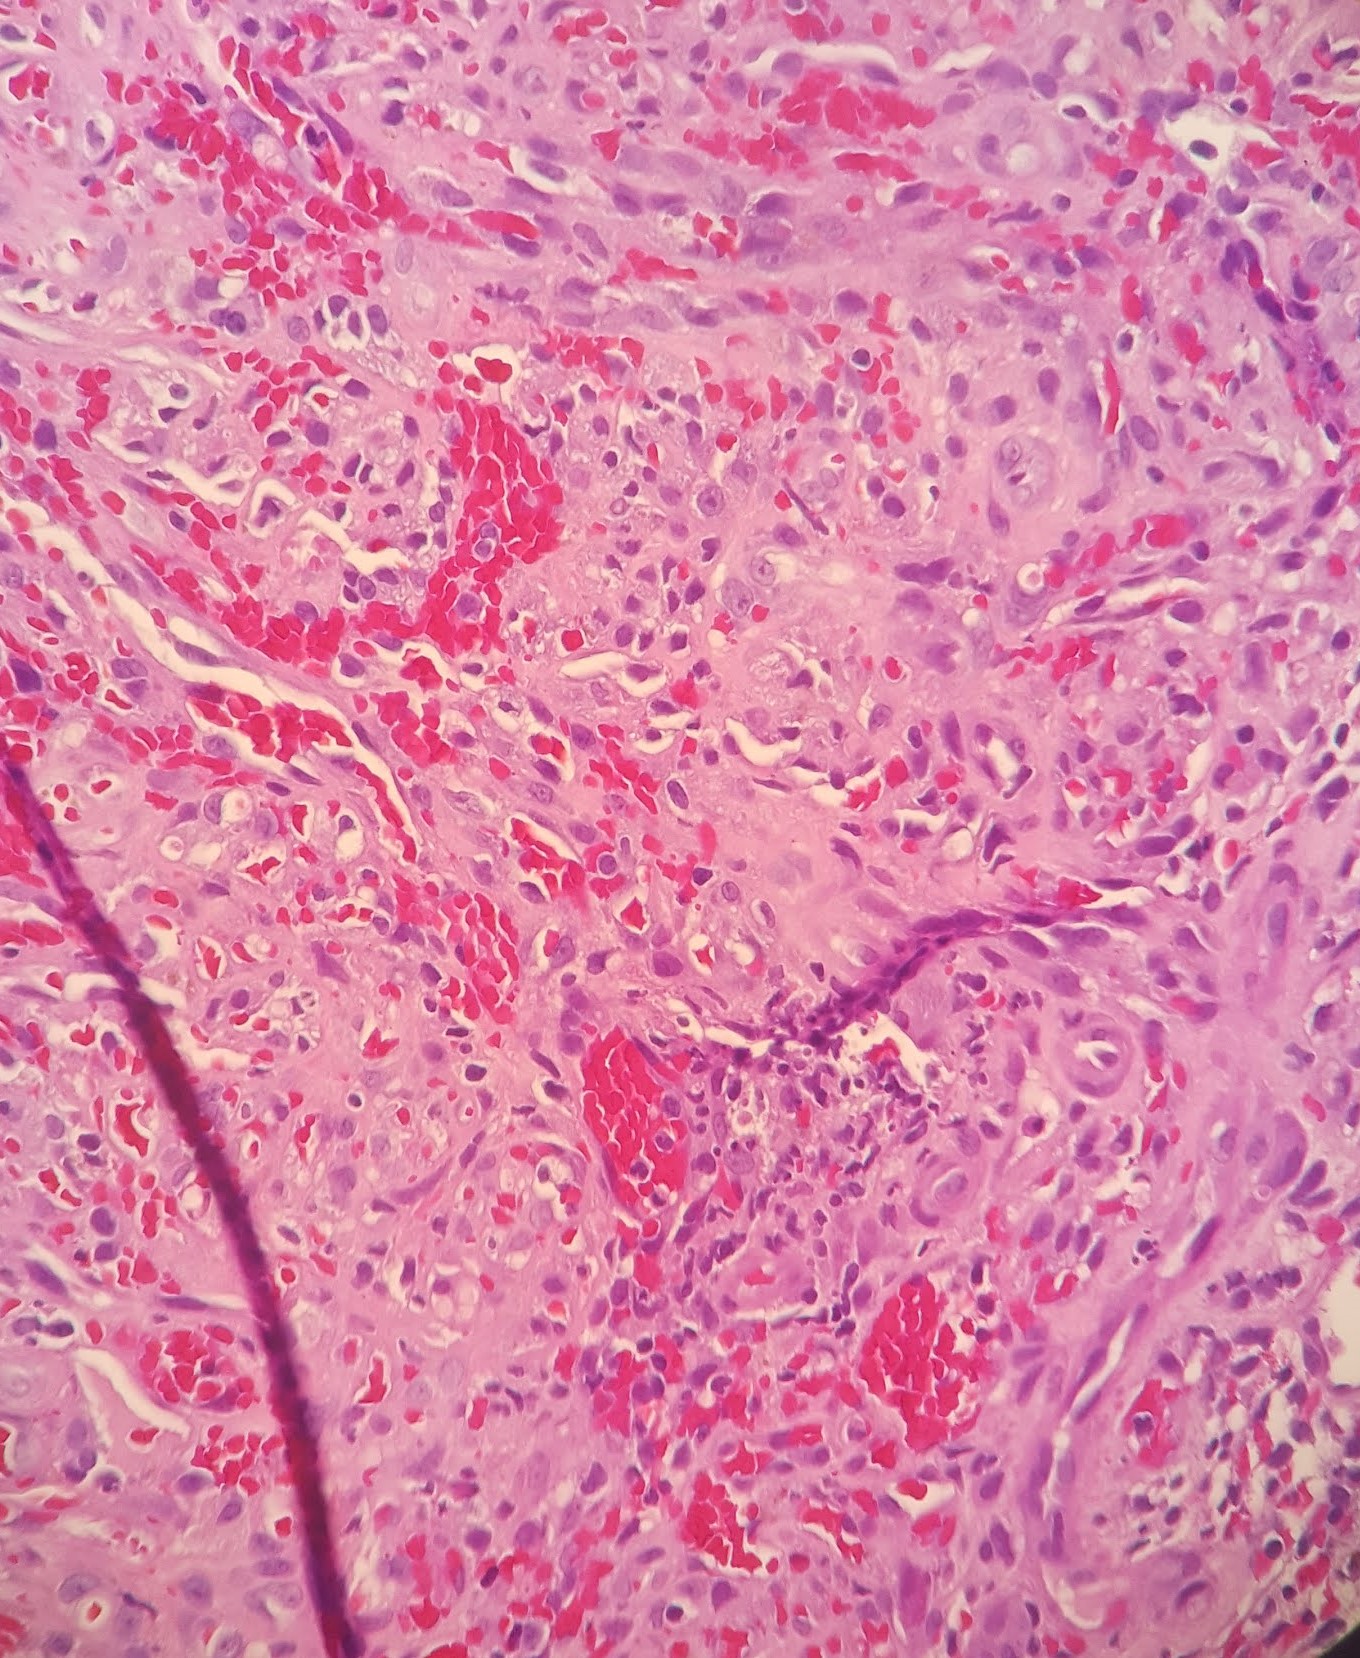

Microscopic examination reveals the following.

Histologically, Kaposi sarcoma is composed of monomorphic spindle cell proliferation arranged in a vague fascicular appearance with intervening slit-like spaces. Intracellular and extracellular eosinophilic PAS+ (diastase-resistant) hyaline globules are present as well as extravasated red blood cells. HHV8 (LANA) immunohistochemical stain can confirm the diagnosis. Treatment is variable based on the extent of the patient’s disease.